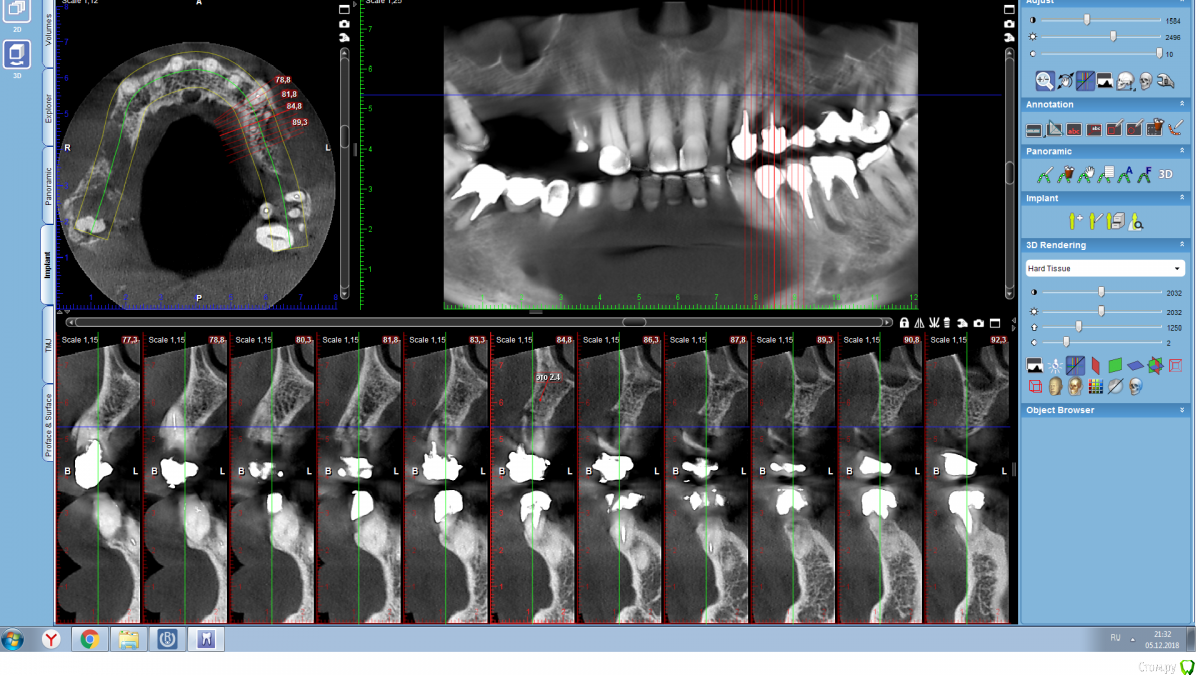

Serg2018 Опубликовано 28 ноября, 2018 Автор Поделиться Опубликовано 28 ноября, 2018 Вот пытаюсь выложить несколько срезов КТ правой стороны, надеюсь, я это правильно понял, делаю впервые. Также тыкал мышкой и она мне что-то замеряла, если в мм, то получается, что в самой тонкой части толщина 2,8 мм? или это я все неправильно понимаю? Ссылка на комментарий

Nazim_NV86 Опубликовано 28 ноября, 2018 Поделиться Опубликовано 28 ноября, 2018 (изменено) Sirona Galileos ?Должно быть окно, где срезы видны как распил. Сечение. Лучше на этом измерять. Можете всю томограмму загрузить на яндекс диск и выложить ссылку. Но сначала проверьте как работает запуск. На той программе, что выше написал, запуск скорее всего возможен только с диска. Если среди файлов на диске есть файл DCM, то его одного достаточно. Просмотрщик не нужно выкладывать. Изменено 28 ноября, 2018 пользователем Nazim_NV86 Ссылка на комментарий